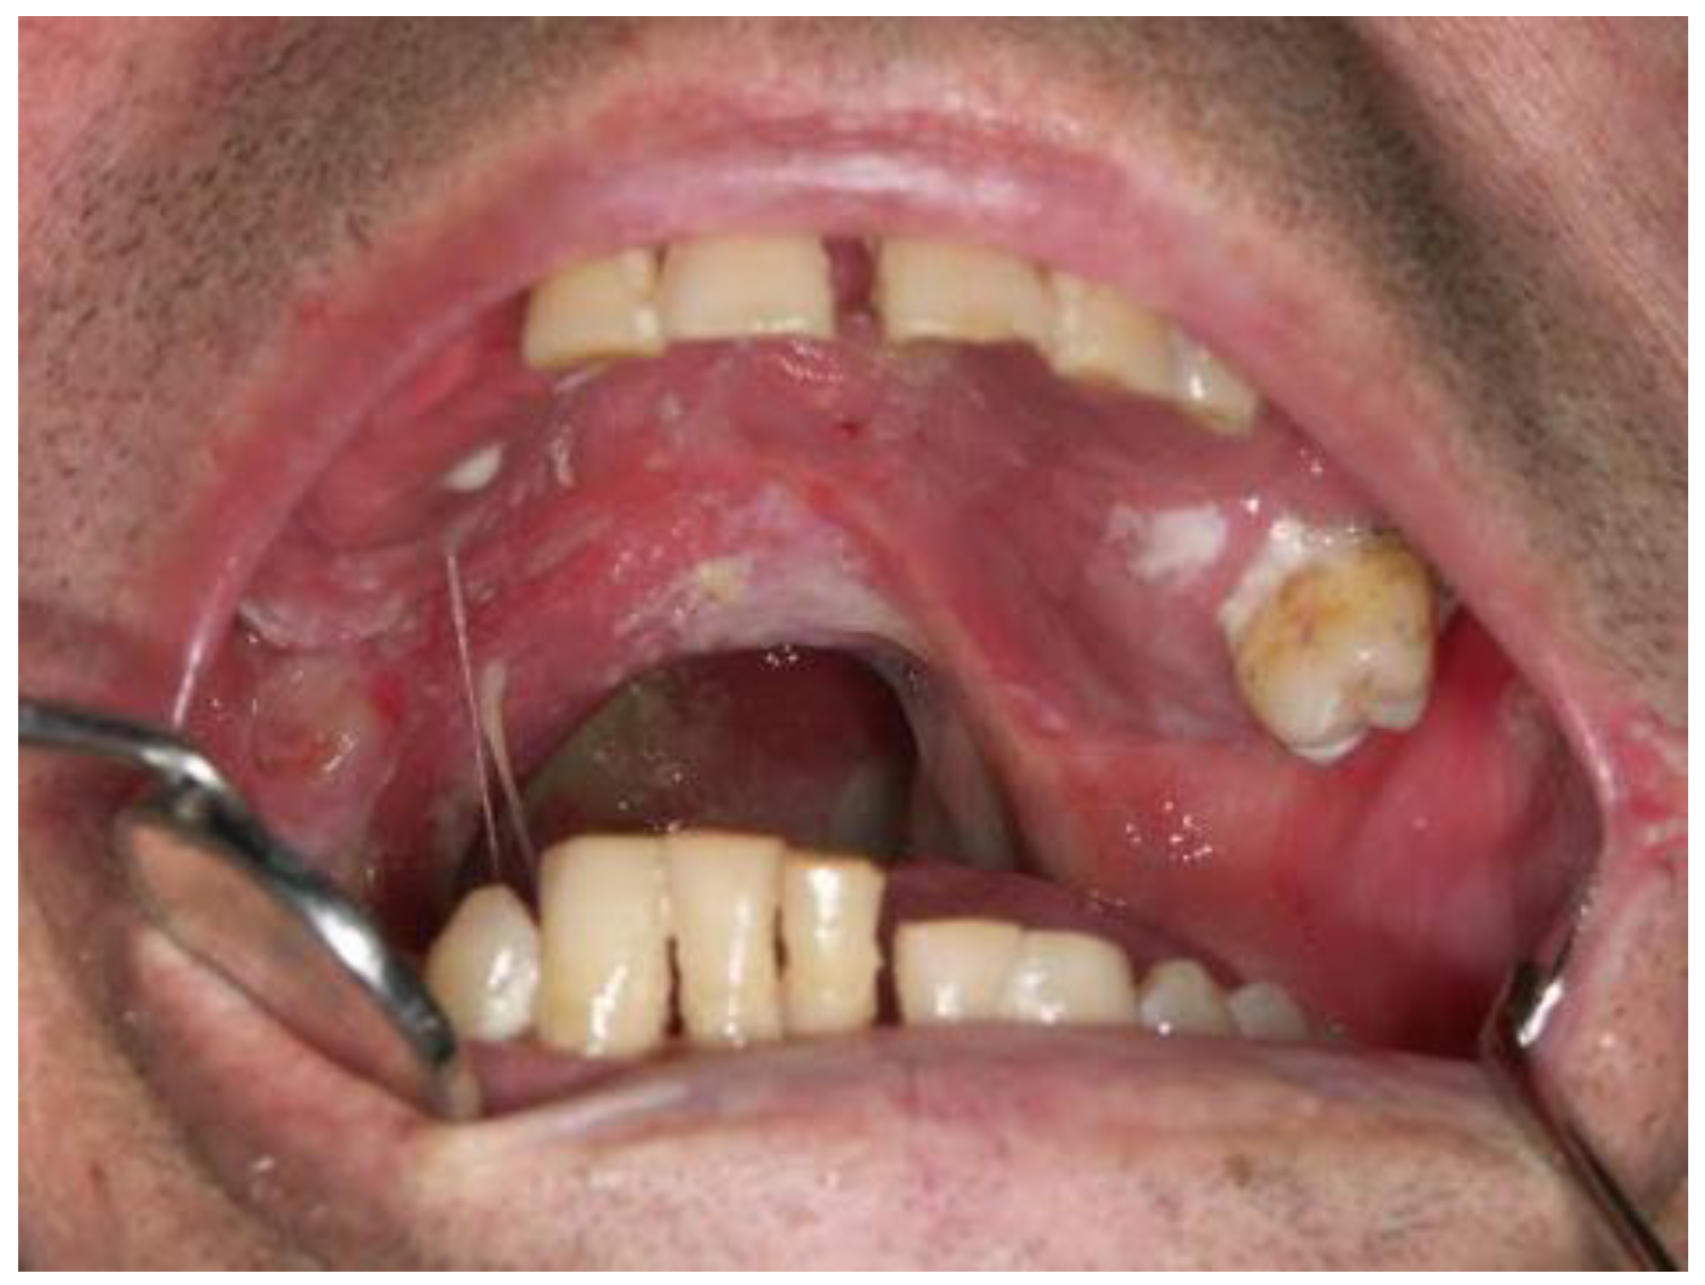

Oral Manifestations of B-Complex Vitamin Deficiency

Oral Manifestations of Vitamin C Deficiency